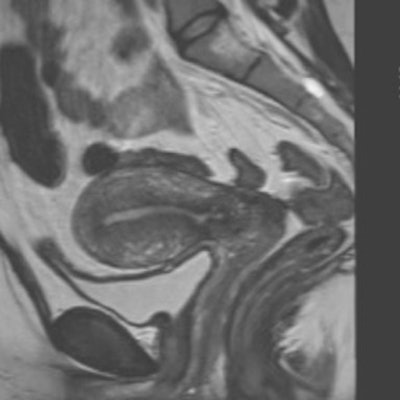

The study included 31 patients who were imaged using a 1.5-tesla MR system (Magnetom Avanto, Siemens Healthcare). They imaged in the supine position with a phased-array surface coil and received 20 mg of intravenous hyoscine butylbromide (Buscopan, Boehringer Ingelheim) just prior to imaging to minimize bowel peristalsis. High-resolution 3D T2-weighted images were obtained in the coronal plane.

Two experienced radiologists independently assessed image quality and disease extent in the 31 patients. Both were blinded to patient identity, previous imaging, and menstrual status. Interobserver agreement was assessed using the kappa (κ) test.